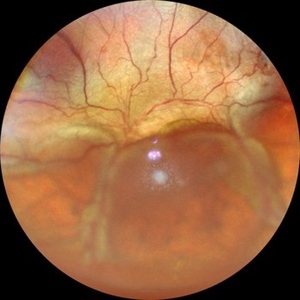

Von Hippel-Lindau Syndrome

Jul 12 2021 by Akansha Sharma

Color photo montage of a 19-year-old female with Von-Hippel-Lindau syndrome.

Photographer: Dr. Akansha Sharma-Retina Foundation, Ahmedabad

Condition/keywords: angioma, Von Hippel-Lindau